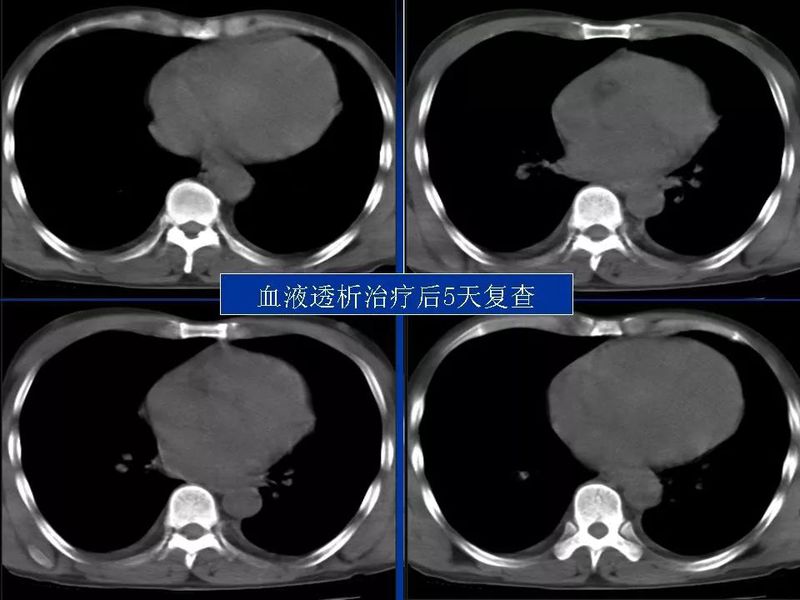

主任提醒:这个病很容易误诊为肺炎!